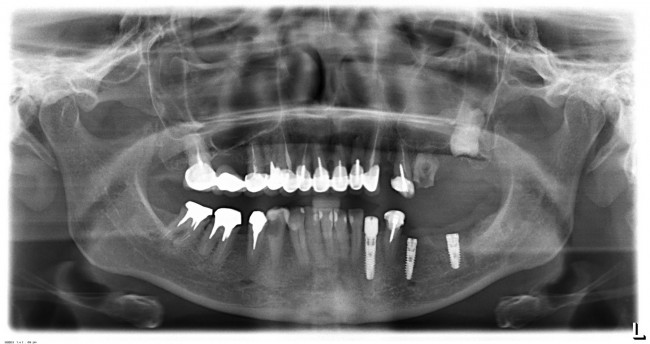

Стоит ли сейчас приступать к третьему и четвертому этапам, а именно — к удалению зубов и имплантации на правой стороне? На мой взгляд, нет. И тут срабатывает принцип, поспешишь — людей насмешишь. Ну подумайте сами — у пациентки не интегрированы импланты с левой стороны, вся жевательная нагрузка приходится на правую сторону. Удалив зубы, мы сильно увеличим нагрузку на оставшиеся передние сегменты, которые, если честно, находятся не в лучшем состоянии. И это не говоря о том, как пациентка будет себя чувствовать, не имея возможности нормально пережевывать пищу. Поэтому в наших интересах — дождаться интеграции имплантов слева, установить на них временные протезы, перенести на них жевательную нагрузку, и только потом приступать к работе на правой стороне.

И тут пациентка сказала: «Постойте! У меня так легко проходят операции, так почему бы нам не поставить большее количество имплантов в правой части? В идеале, чтобы каждая коронка опиралась на свой имплантат — я больше не хочу мостовидные протезы!» Желание пациента — закон. Поэтому на правой стороне мы усложняем работу:

Как вы думаете, сколько времени заняла третья хирургическая операция? 60 минут! Легко, быстро и комфортно. А главное — результативно!

В дальнейшем, после протезирования нижнего правого сегмента, мы, скорее всего, вернемся в левую часть и реализуем схему «одна коронка-один имплантат», поскольку это дает лучшие в эстетическом и функциональном отношении результаты. Ну и, пациентка так захотела.

Что в итоге получилось? Пока три этапа, по 60-90 минут каждый. Минимум времени операции, минимум травмы. Как результат — успешное комфортное лечение с высокой эффективностью и без больших единовременных затрат. Это всяко лучше, чем одна многочасовая дорогостоящая операция с тяжелым послеоперационным периодом и существенным дискомфортом. Вот вы бы что выбрали?